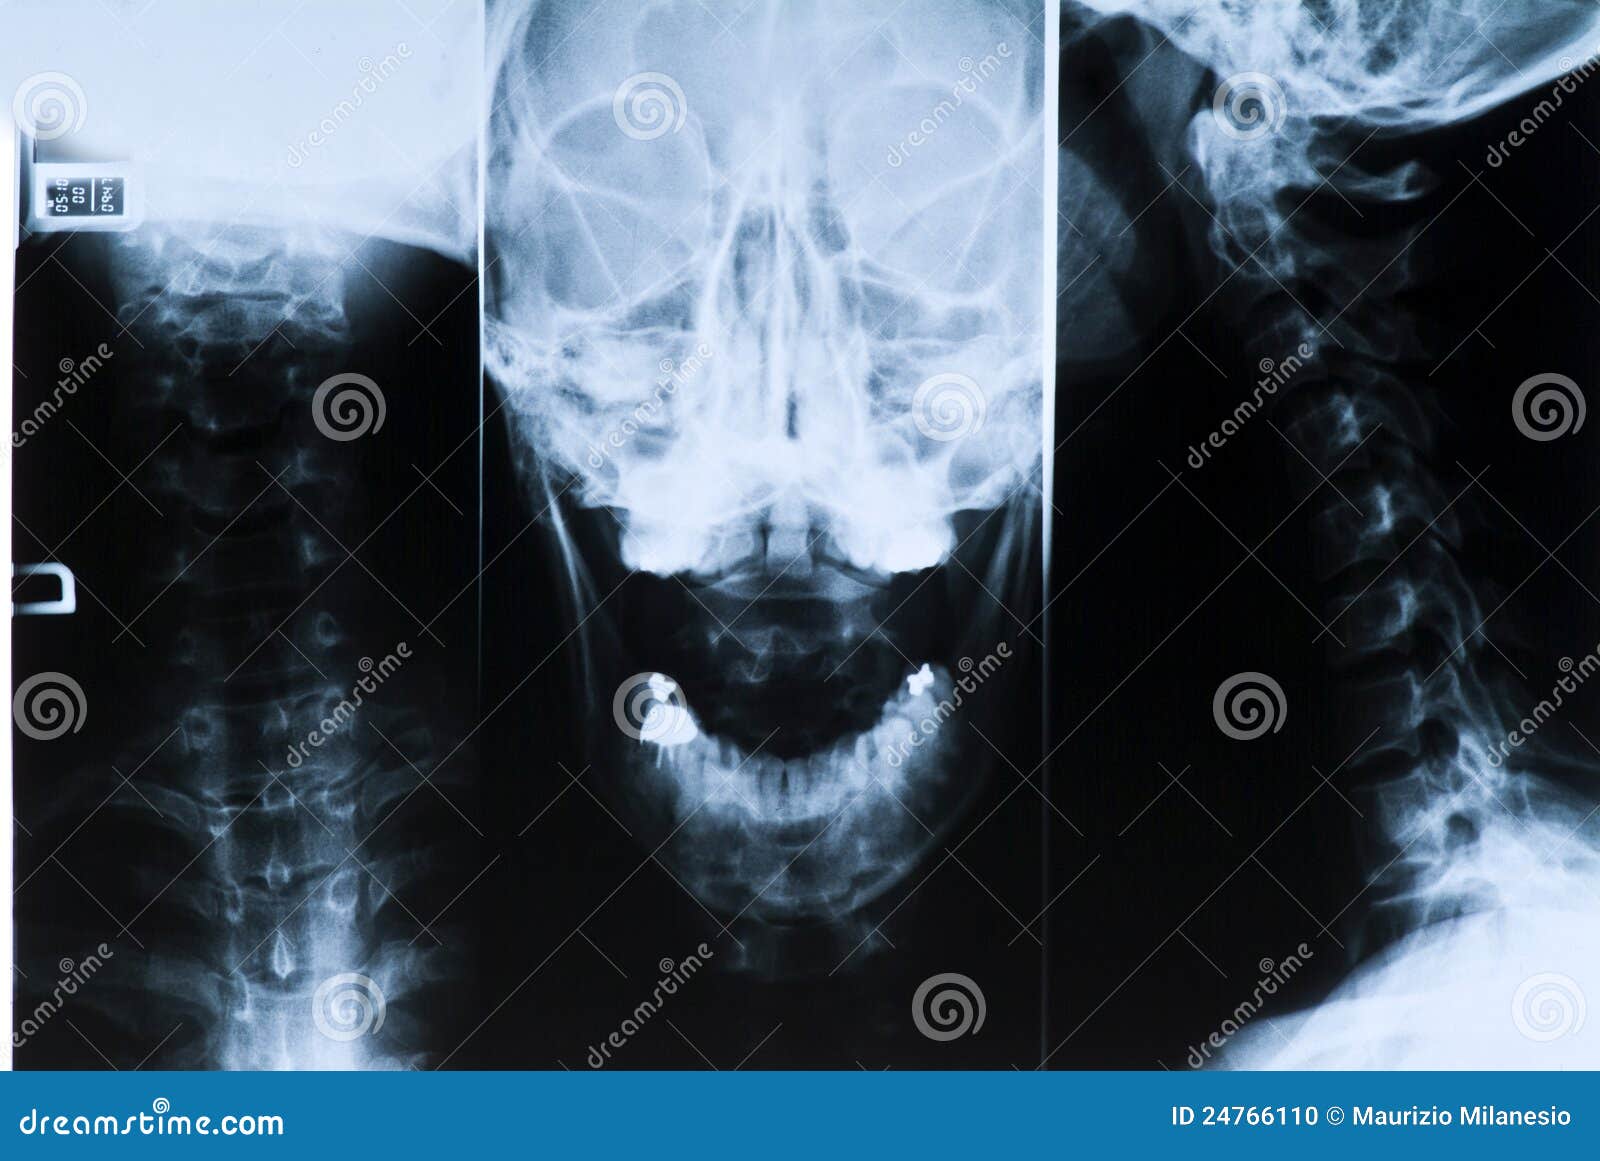

Radiografia Della Testa E Del Collo Foto Foto Stock Gratis E Royalty Free Da Dreamstime

Radiografia Della Testa E Del Collo Fotografia Stock Immagine Di Malattia Osso